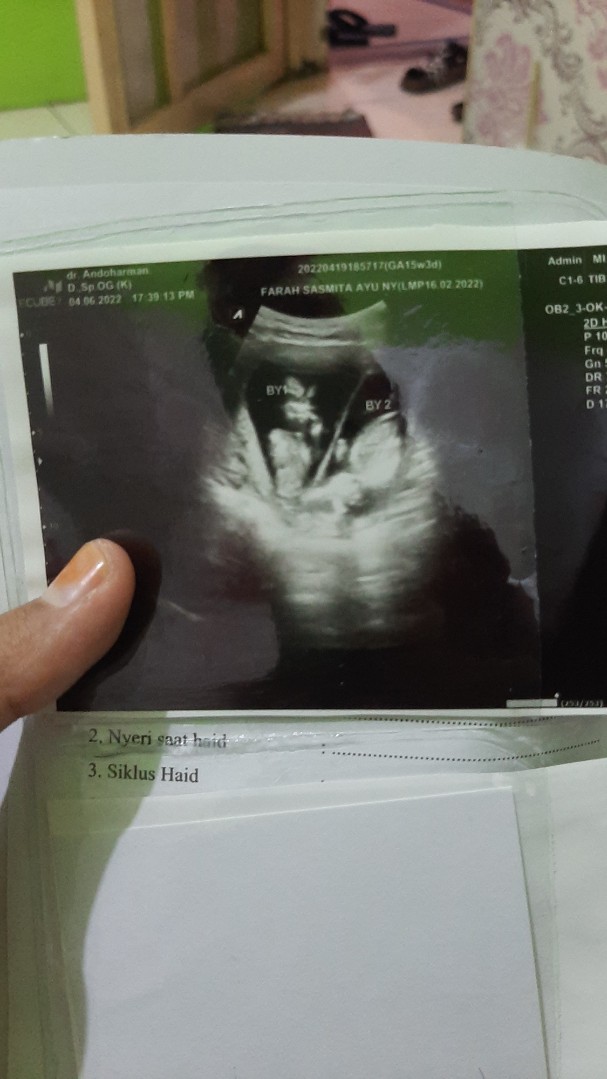

Saya mau tanya saya sedang hamil kembar dan ada penyekatnya apakah itu hamil identik atau bukan

kalau kembar identik biasanya 1 sel telur dibuahi 2 sperma, kalau tidak identik 2 sel telur dibuahi 2 spermam kalau ga salah gitu. tapi bunda bisa cek di yt atau google.